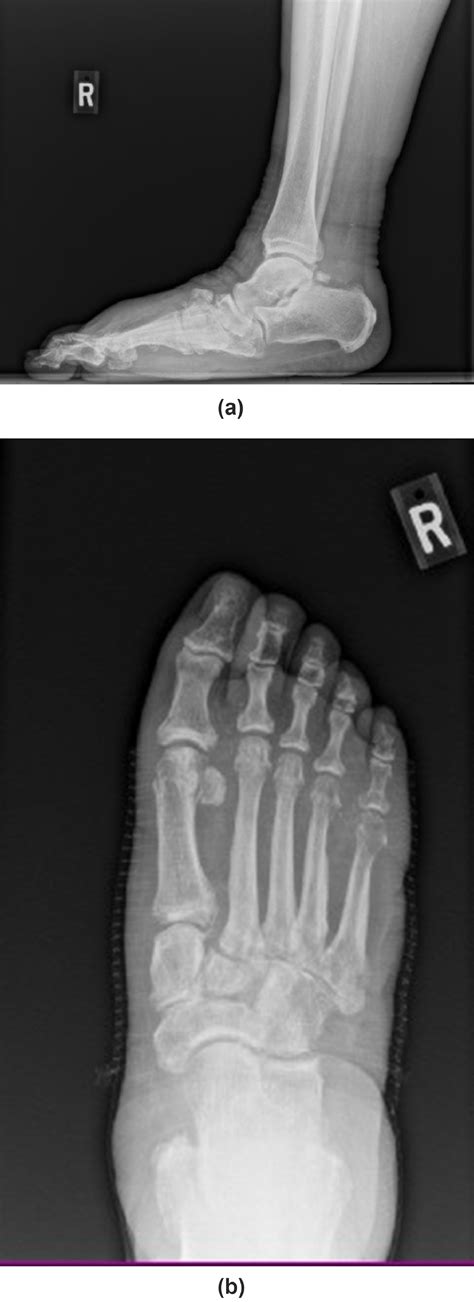

At its core, Charcot Arthropathy Foot is a progressive condition. Because the patient cannot feel the micro-traumas caused by everyday movement, the joints begin to weaken and collapse. The bones may fracture, shift, or even dislocate, causing the foot to lose its natural arch and shape. In the medical community, this is frequently described as a "rocker-bottom" deformity, where the middle of the foot drops, creating a convex shape on the sole.

Diagnostic Procedures and Clinical Evaluation

Doctors typically diagnose Charcot Arthropathy Foot through a combination of clinical history and imaging. Physical exams are used to assess the range of motion and look for signs of neuropathy. Imaging is critical to differentiate Charcot foot from cellulitis or other bone infections.

X-ray Detects fractures, dislocations, and bone fragments.